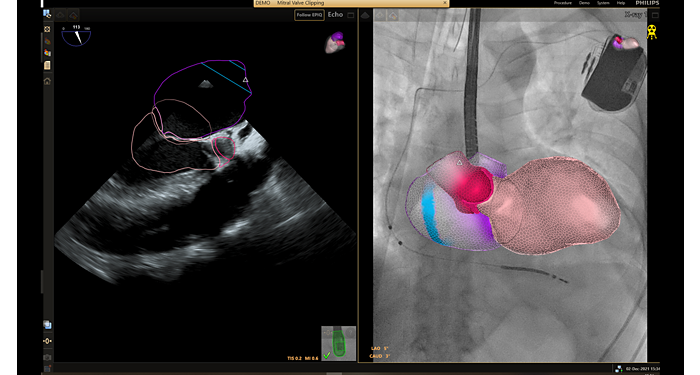

Anatomical Intelligence looks at a patient’s ultrasound data and applies adaptive system intelligence using 3D anatomical models to create easier and more reproducible results. Anatomical Intelligence in ultrasound uses advanced organ modeling, image slicing, and proven quantification to help make ultrasound exams easier to perform and more reproducible while delivering new levels of clinical information to meet the economic and clinical challenges of today’s healthcare environment.

HeartModelᴬ⋅ᴵ⋅ is a new premier Anatomically Intelligent Ultrasound (AIUS) application that automatically detects, segments and quantifies the left ventricle and left atrium volumes and ejection fraction, from the same Live 3D volume. HeartModelᴬ⋅ᴵ⋅ brings advanced automated quantification, 3D views, and robust reproducibility plus time-savings of up to 82% to everyday echocardiography.

Anatomical Intelligence is used in Philips imaging solutions such as EPIQ, Affiniti, and EchoNavigator. Already today it is providing clinicians with sophisticated, yet easy-to-use processing tools, and helping them quickly and more confidently identify anatomy and anomalies, assess disease states, determine treatment, and guide interventions.